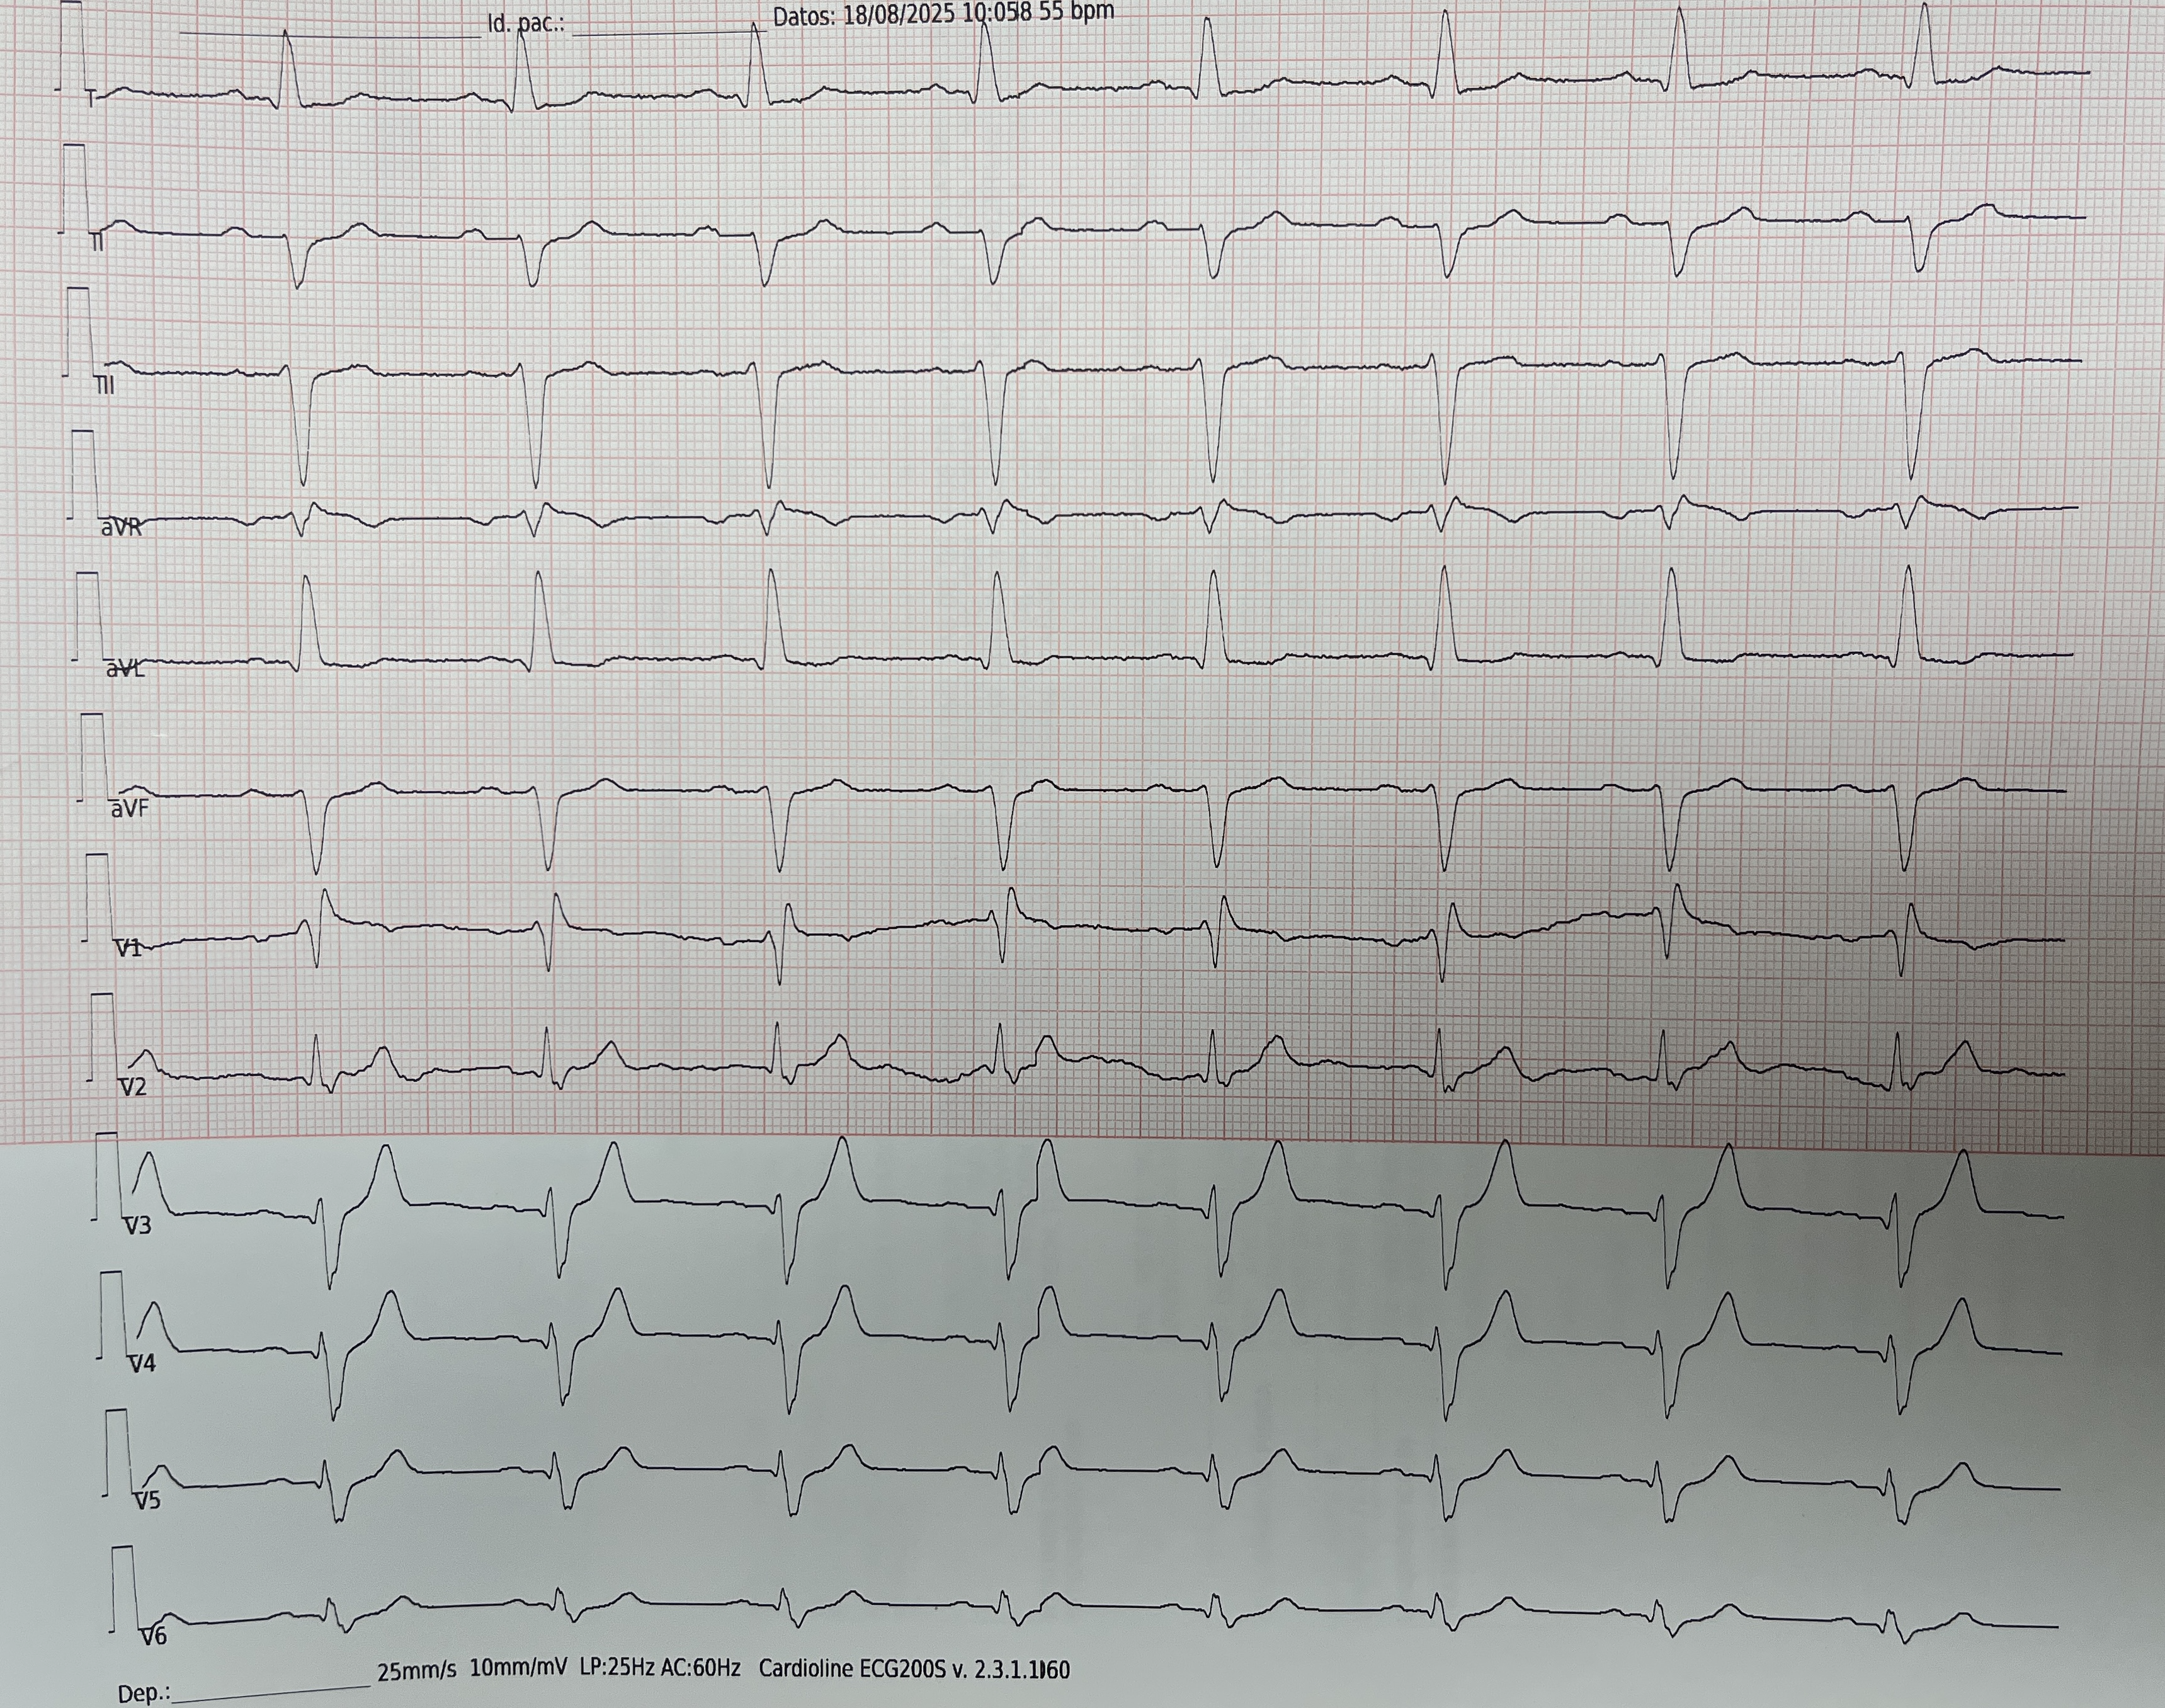

Con este material deberíamos ser capaces de poder realizar el abordaje inicial esta paciente, que se presenta al Servicio de Urgencias con motivo de consulta: Síncope.

Y también deberíamos poder abordar a este paciente: